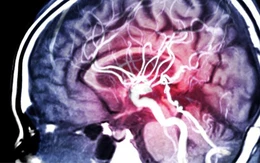

Hỏi chuyện sức khỏe